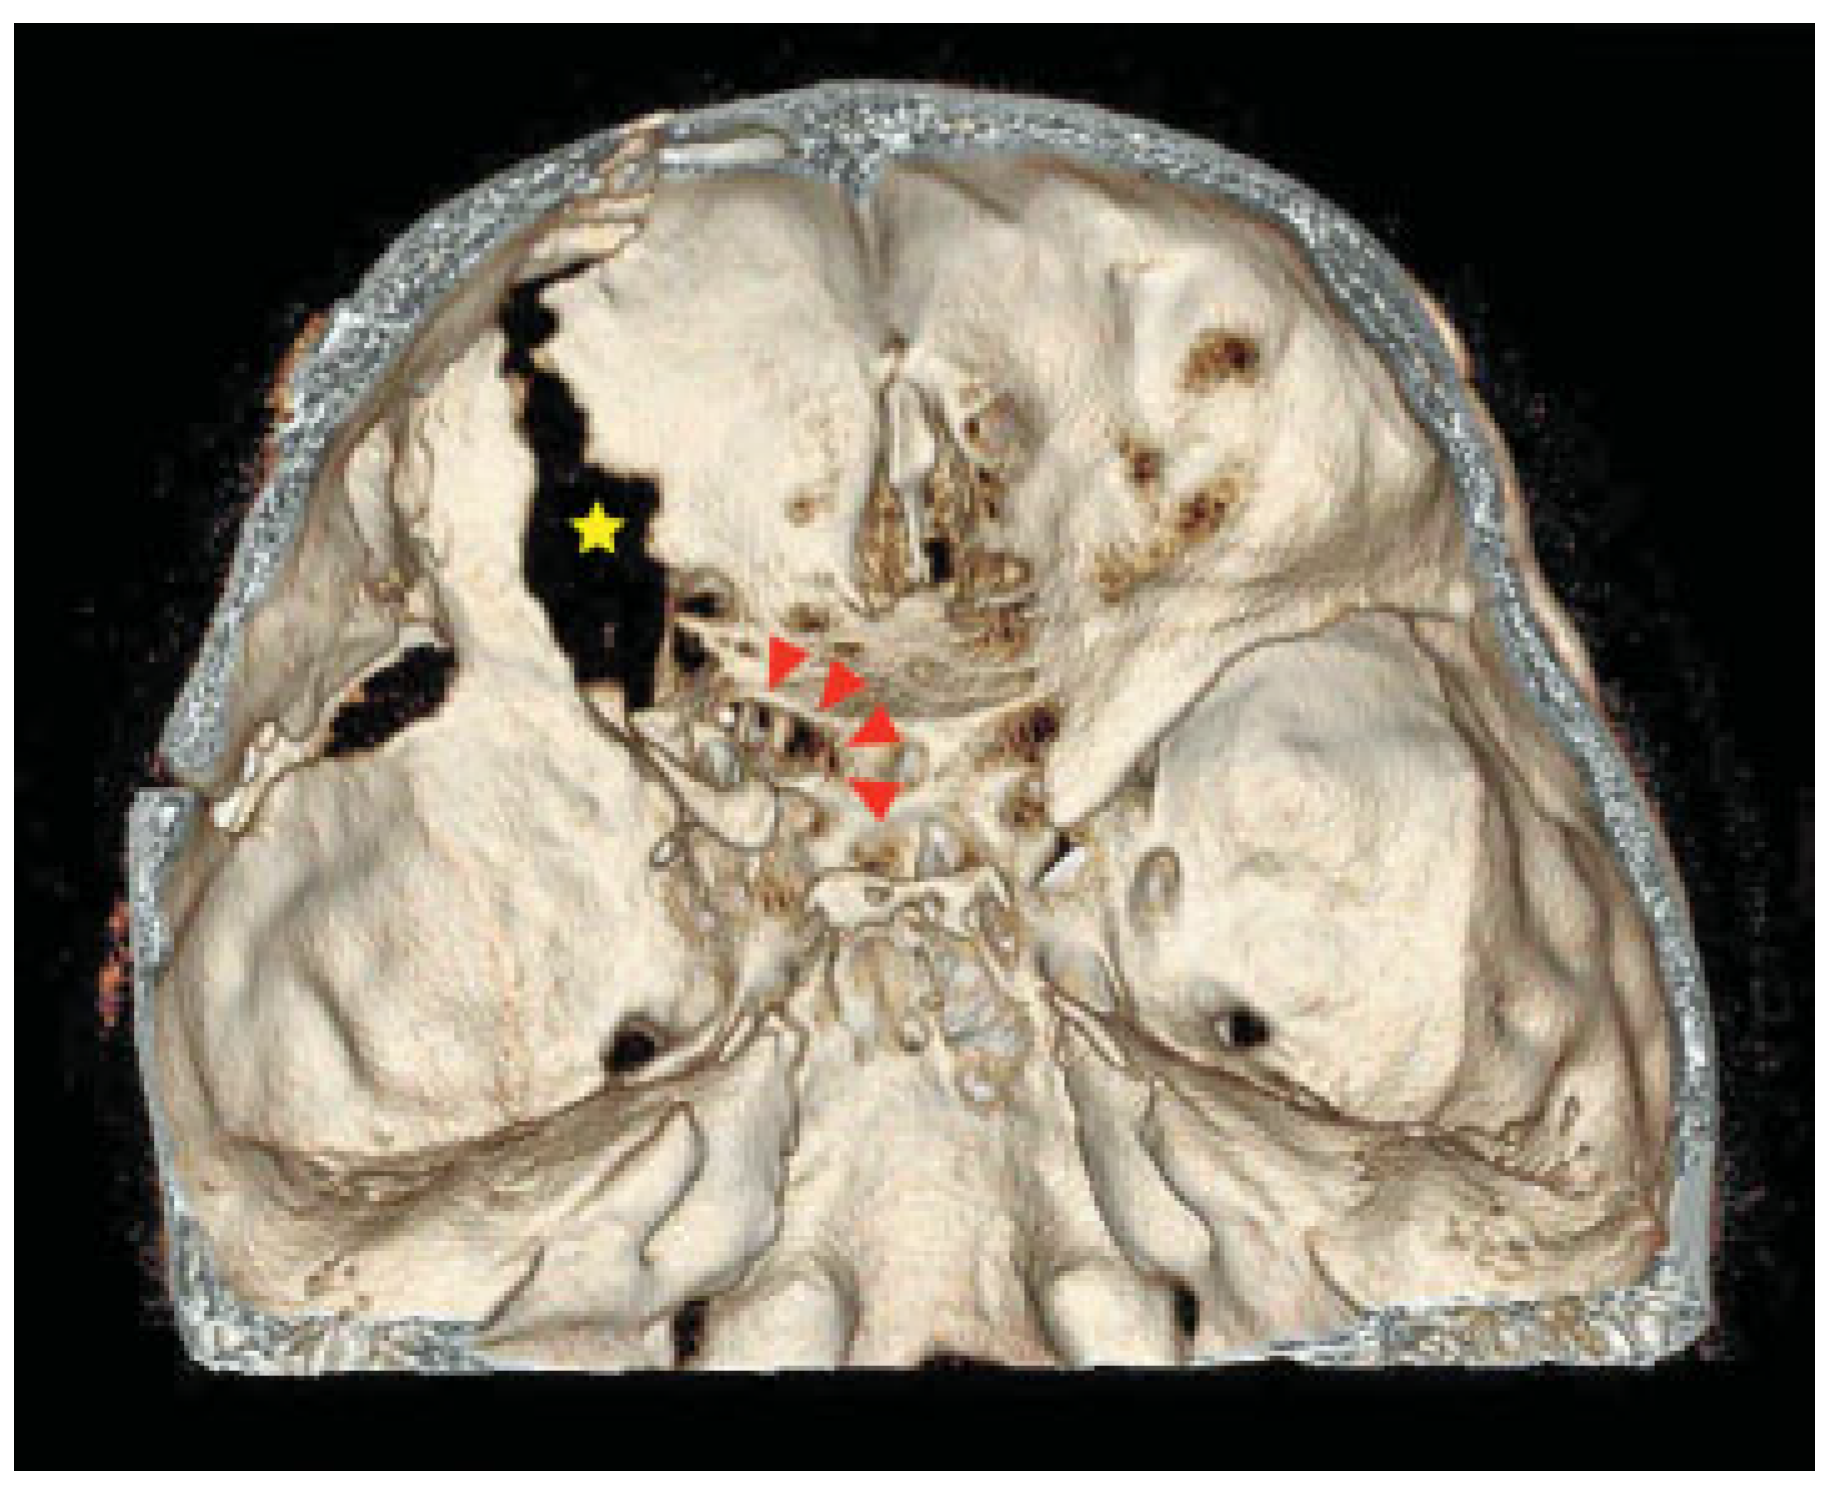

Surgery began six hours after his accident. First, using a coronal incision, the medially displaced left zygoma and inferiorly displaced superior orbital rim fractures were reduced to decrease the elevated orbital pressure and to relieve the compression of the superior orbital fissure. A frontotemporal craniotomy was made. The lesser wing of the sphenoid and the base of the left anterior clinoid process were widely resected sequentially by the epidural approach (Figure 4). Sufficient decompression of the superior orbital fissure and the optic canal was accomplished successively (Figure 5 and Figure 6). Finally all the fractures were reduced and fixed with titanium plates. The left orbital floor was reconstructed with the calvarial bone graft. After surgery, the patient had a dexamethasone taper over six days to reduce cerebral edema, beginning with a dose of 4 mg/day, on the advice of our neurosurgical consultant.

Figure 6.

3D-CT after surgery with decompressed optic canal (red arrowheads) and superior orbital fissure (yellow ☆).